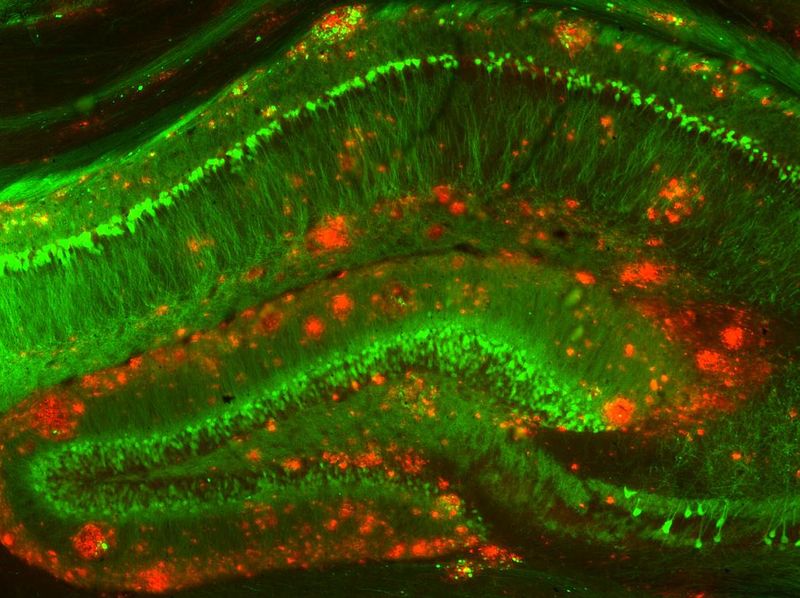

By analyzing the patient’s cerebrospinal fluid and blood, the doctors concluded she was suffering from variant Creutzfeldt-Jakob disease (vCJD), which was later confirmed during her postmortem. This is a rare condition that’s caused by a mysterious infectious agent known as a prion (or proteinaceous infectious particles).

Surprisingly little is known about prion diseases, although scientists do know they arise when certain proteins found on many types of cells begin to misfold in the brain. These misfolded prions can run amok by changing the shape of other neighboring proteins, which go on to become misfolded prions, further spreading the “damage”. Unlike other infectious agents, such as bacteria, fungi, or a virus, they do not contain any DNA or its relative RNA.

Cases of vCJD are exceptionally rare. Just a few hundred cases of vCJD have ever been confirmed, the majority of which we’re linked to the BSE (commonly known as “mad cow disease”) outbreak that originated in the UK during the 1990s and 1980s. In most vCJD cases, humans acquire the misfolded prions by ingesting brain tissue from animals infected with non-human prion disease. It was suspected that the woman could have eaten contaminated beef from this UK crisis, although the case study concludes the risk of this is “ negligible or nonexistent” given the timing of the illness.